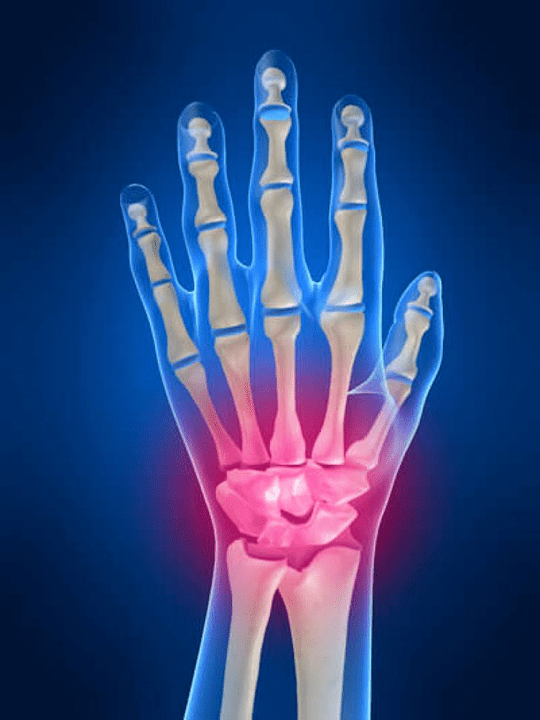

Anatomy of the joints of the hand

All joints of the hand are customary to divide into the following groups:

- wrist combination;

- combinations of the wrist;

- Carpal patterned compounds;

- Mixed compounds;

- Phalanal-Phalanx joints;

- Interponerx compounds.

Wrist joint

The wrist joint is formed by the bones of proximal bones (up) a number of wrists (trihedral, semi-liquid, skaphoid bones) and distal areas of radiation and elbow bones.Elbow bone is not directly attached to wrist bones but with distal help (Down) article disk.This structure separates the gap of wrist combination from distal cavity (Down) Tile joint.